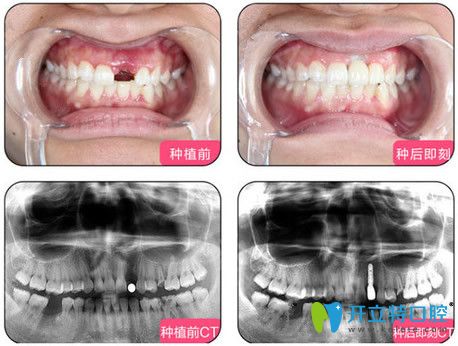

一、單顆種植牙案例:

單顆種植技術(shù):適用于單顆不相鄰的牙齒缺失,年輕人牙齒意外掉落的修復(fù)。

烏魯木齊凱樂口腔單顆種植牙效果圖